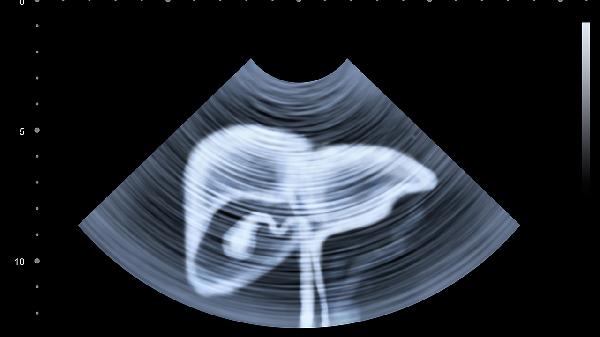

肝脏的代偿能力超强,只有30%健康细胞就能维持基本功能。正因如此,我们更要学会识别这些细微信号。建议40岁以上人群每年做一次肝脏超声和肝功能检查,乙肝携带者要缩短到半年一次。记住,养护肝脏最好的时机是十年前,其次就是现在。从今晚11点前入睡开始,给这个默默工作的器官一个修复的机会吧!